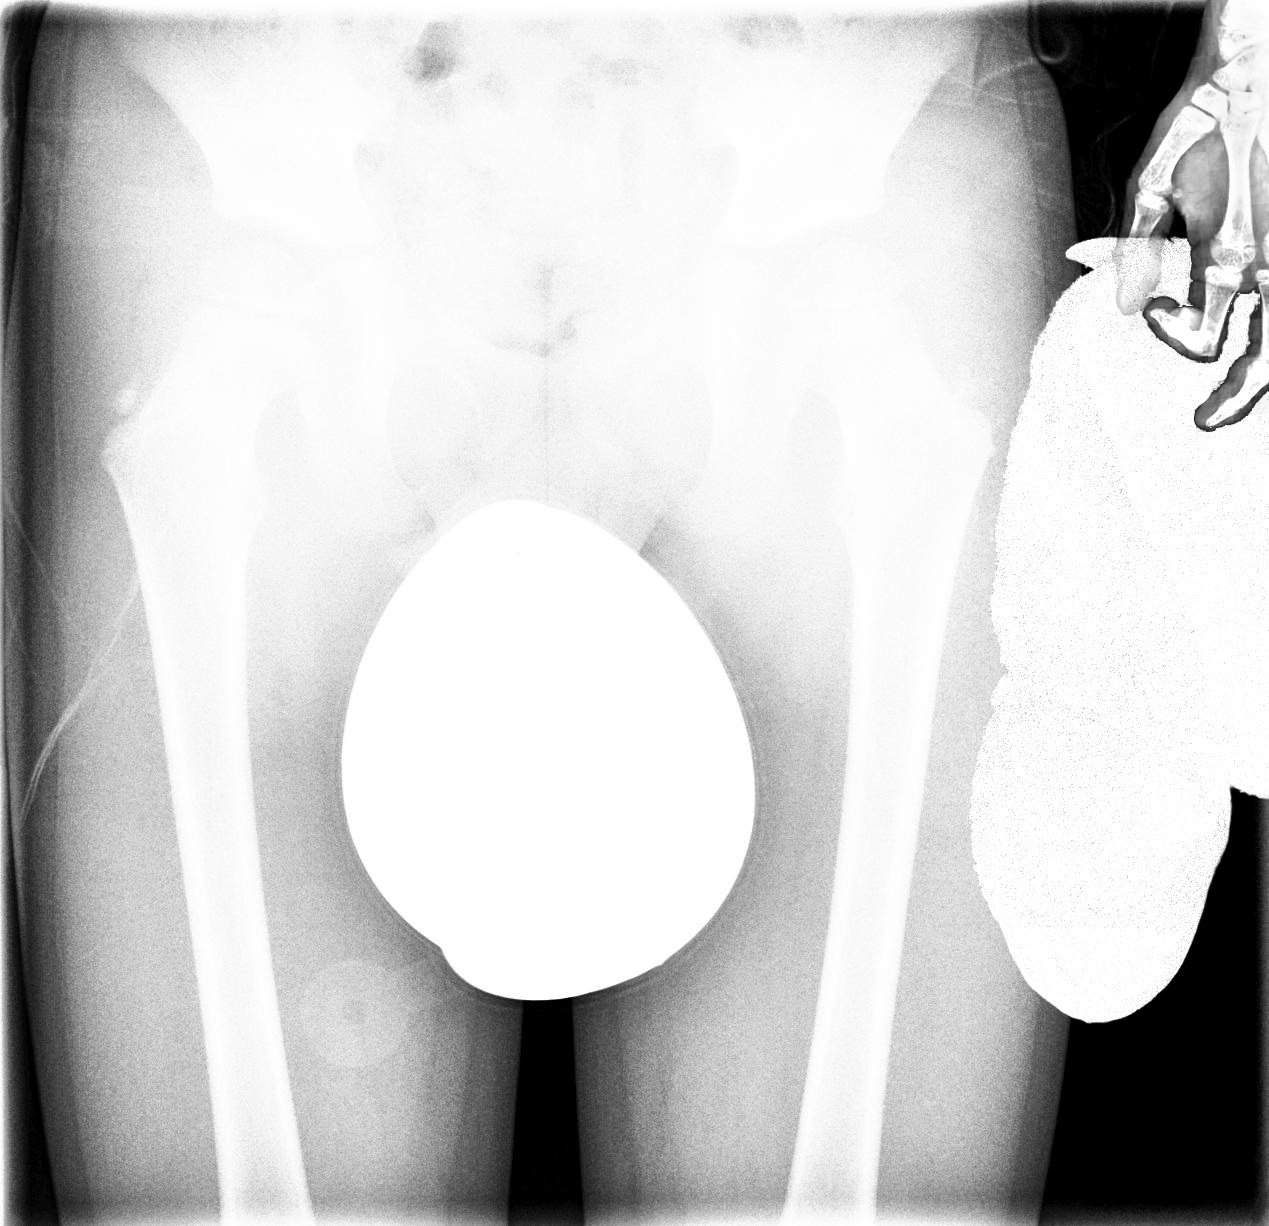

Groeipijn

Work in progress.